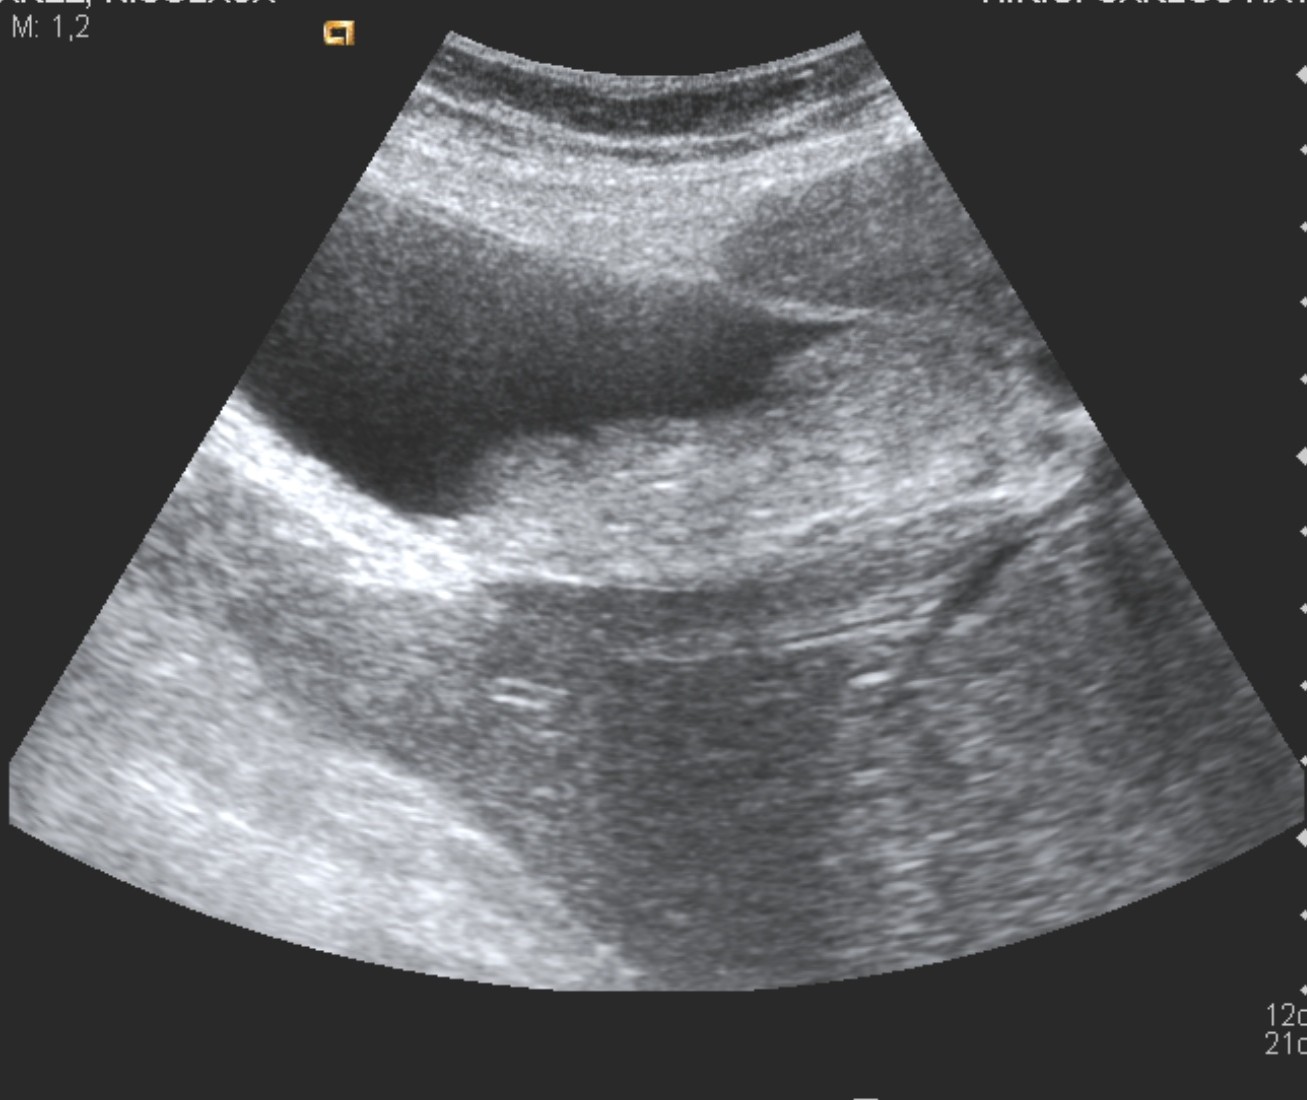

Ante el cuadro actual se decide realizar Ecografía, se observa lo siguiente:

Se obeserva en la primera imagen la vesícula biliar con contenido ecogénico en su interior sugerente de Barro biliar.

En la segunda imagen se aprecia el colédoco con un calibre aumentado de 13 mm con una imagen en su interior hiperecogénica con sombra posterior, de 13,9 x 17,2 mm aprox, bien definida y de bordes bien delimitados compatible con cáclculo biliar en su interior.

El resto de la exploración ecográfica no aportó alteraciones de sinificación.

COCLUSIÓN: Hallazgos compatibles con litiasis biliar por barro y Coledocolitiasis en un paciente con clínica de cólico biliar complicado.